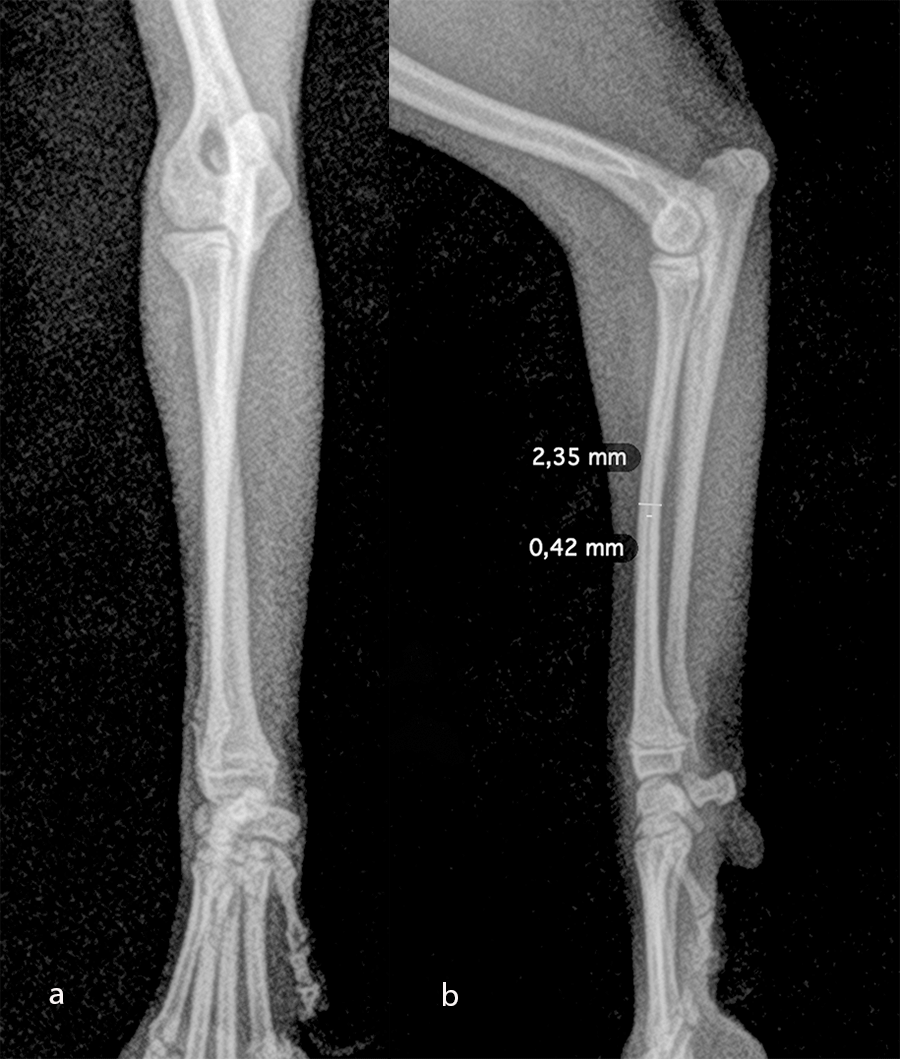

The patient was a 6-month-old, 1 kg (exactly 0.950 kg) Pomeranian dog presenting with a radial fracture of the left thoracic limb after a jump from ≈ 50 cm. The 1.5 mm System was too large for the width of the radius (2.2 mm) and the width of the radial medullary canal (0.5 mm) (Fig 7). The 1.3 mm adaptation plate was a perfect plate for this fracture. This plate option permitted the use of cortex and locking screws.